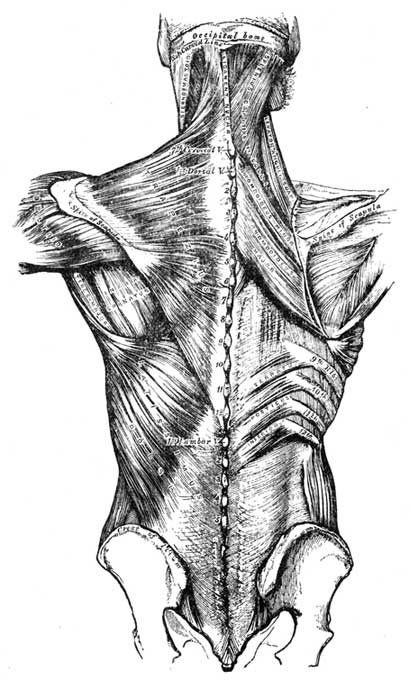

1. Vertebral Column; 2. Skull; 4. Sternum; 7. Collar Bone; 15. Hip Bone; 16. Sacrum; 18. Femur; 19. Knee Pan; 21. Fibula; 22. Tibia; 8. Humerus; 10. Radius; 11. Ulna.

Treatment may also be given for lack of assimilative power. The back, especially on either side of the spine, is rubbed with gentle pressure and hot olive oil. This pressure is so applied that a genial heat arises along the whole spinal column. This done twice a day, for half-an-hour at a time, and continued for several weeks, will markedly restore assimilative power. Cases which have been perfectly helpless for eight and even ten years are cured by this simple method, sufficiently and carefully followed.

A little thought will enable any one to distinguish between pains due to back failure and those due to local causes. If there is no appearance of anything wrong at the part pained, then the evil is probably in the back. It is even a good rule to consider the pain at first as due to back failure rather than local causes, for by treatment of the back the local trouble, when that is present, is much helped and relieved.

In the case of pains in the arms or hands, the upper part of the back is indicated; in leg and foot troubles, the lower part. Neuralgic pains are almost always of this class.

In any case of this kind, heat may be applied to the spine, and rubbing with hot oil given to it, at its upper or lower part as required. If the heat and rubbing increase the pain, then cold applications may be used. Sometimes heat and cold may be needed alternately; but common sense must guide, and all irritation or chilling of the patient must be carefully avoided.

The best manner of applying cold to the spine is described in article on Angina Pectoris. Towels are folded as there directed. The moist one (well wrung out) is placed next the spine, either over the part desired or the whole spine. The dry one is placed over this, and the patient lies down on his back on the top of them; or, if he cannot lie, as sometimes happens, the towels are gently pressed with the hand against the spine until sufficient cooling has resulted. The patient should never be made to shiver. If he feels chilly, hot fomentations to the feet and legs, as described in article on Angina Pectoris, may be applied.